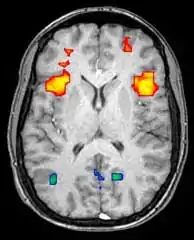

Functional magnetic resonance imaging (fMRI) and arterial spin labeling (ASL) relies on the paramagnetic properties of oxygenated and deoxygenated hemoglobin to see images of changing blood flow in the brain associated with neural activity. This allows images to be generated that reflect which brain structures are activated (and how) during the performance of different tasks or at resting state. According to the oxygenation hypothesis, changes in oxygen usage in regional cerebral blood flow during cognitive or behavioral activity can be associated with the regional neurons as being directly related to the cognitive or behavioral tasks being attended.

Most fMRI scanners allow subjects to be presented with different visual images, sounds and touch stimuli, and to make different actions such as pressing a button or moving a joystick. Consequently, fMRI can be used to reveal brain structures and processes associated with perception, thought and action. The resolution of fMRI is about 2-3 millimeters at present, limited by the spatial spread of the hemodynamic response to neural activity. It has largely superseded PET for the study of brain activation patterns. PET, however, retains the significant advantage of being able to identify specific brain receptors (or transporters) associated with particular neurotransmitters through its ability to image radiolabeled receptor "ligands" (receptor ligands are any chemicals that stick to receptors).

As well as research on healthy subjects, fMRI is increasingly used for the medical diagnosis of disease. Because fMRI is exquisitely sensitive to oxygen usage in blood flow, it is extremely sensitive to early changes in the brain resulting from ischemia (abnormally low blood flow), such as the changes which follow stroke. Early diagnosis of certain types of stroke is increasingly important in neurology, since substances which dissolve blood clots may be used in the first few hours after certain types of stroke occur, but are dangerous to use afterward. Brain changes seen on fMRI may help to make the decision to treat with these agents. With between 72% and 90% accuracy where chance would achieve 0.8%,[14] fMRI techniques can decide which of a set of known images the subject is viewing.[15]